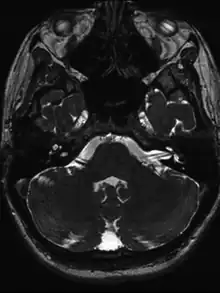

Vessel loop formation on left in a individual with suspected acute vestibular neuritis

• MRI